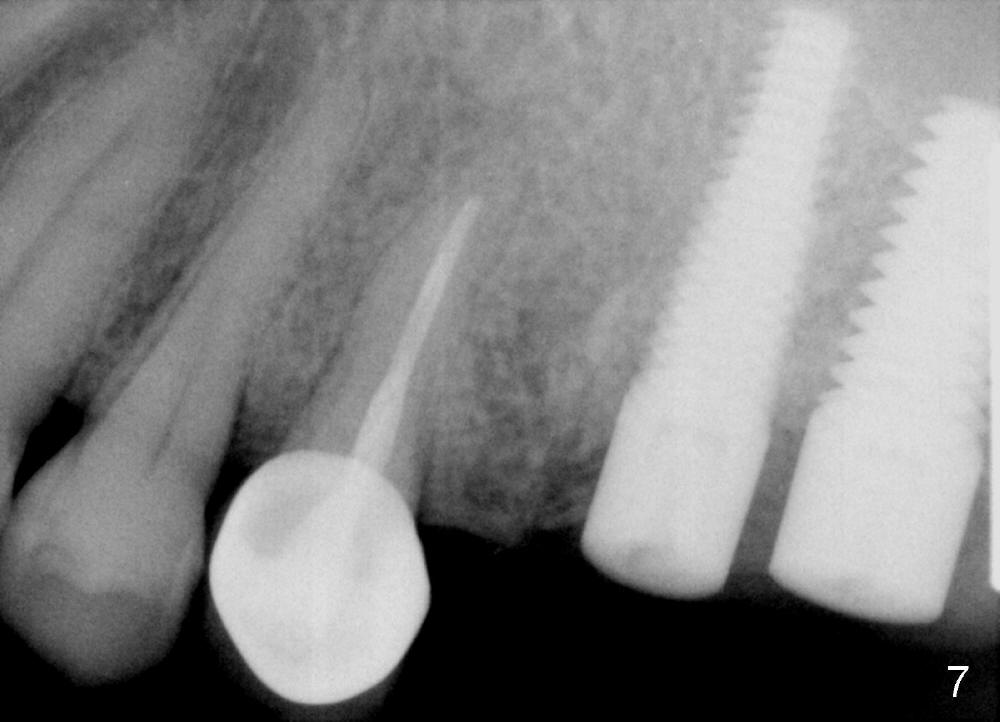

Fig.4 shows the septum between 3 roots (P: palatal, MB: mesiobuccal, DB: distobuccal) after extraction. Osteotomy is formed in the septum mainly by using osteotomes, followed by tap drill (Fig.5: 4.5x20 mm). When a 5x20 mm tap is removed, the osteotomy deviates buccally (Fig.6 arrowhead and MB). Finally a 5x20 mm implant is placed at the site of #14 (Fig.7).